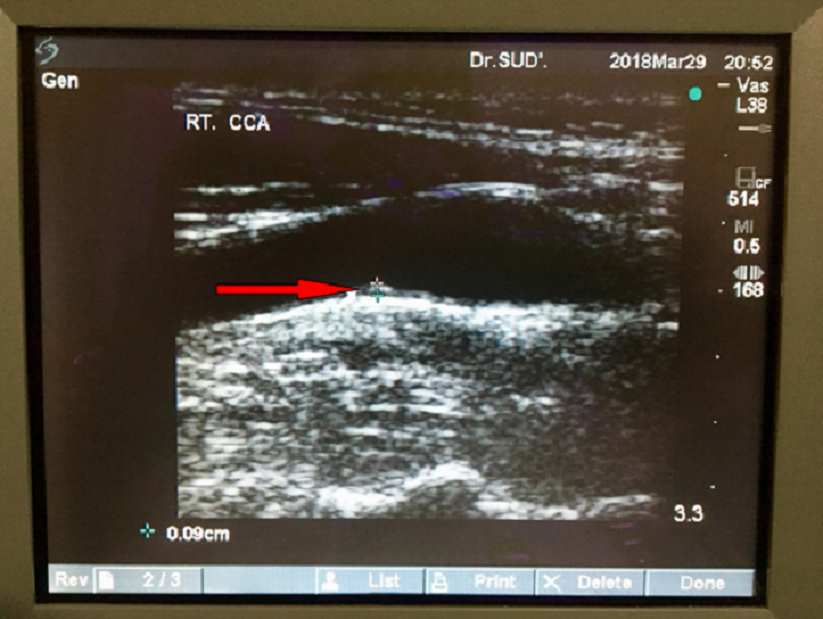

Changes in Carotid Intimal Medial Thickness (CIMT) With Glycaemic Control in Patients of T2DM

Dr. Sanjay Sud

International Journal of Innovative Research in Medical Science·June 27, 2019